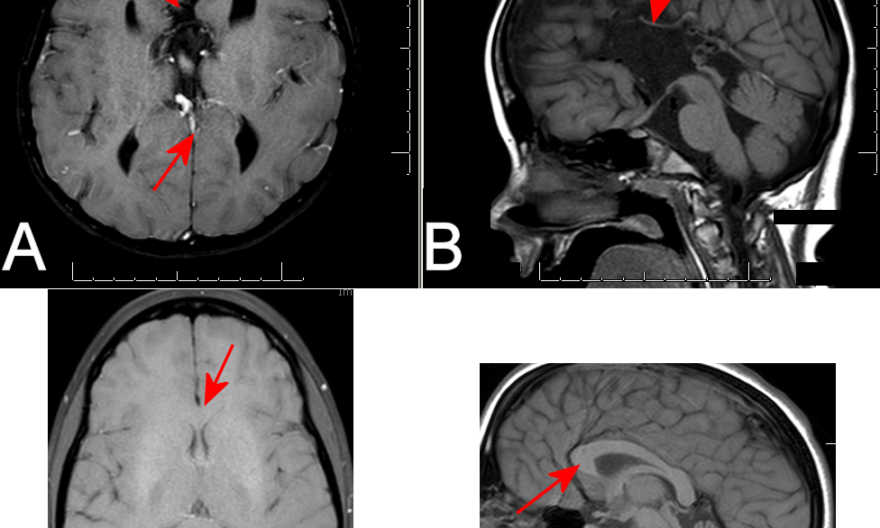

Diagnosis: Corpus Callosum Agenesis

Figure 1: A: Axial T1 image showing no intra-hemispheric connections. B. A mid-sagittal cut showing no evidence of a corpus callosum. Arrows in A and B show where the corpus callosum would normally be found. C and D are shown for comparison, and demonstrate a thick corpus callosum connecting the two hemispheres.

There are some cases in which a very thin corpus callosum exists but is difficult to visualize. In these cases, the gyrus immediately adjacent to the thin corpus callosum would run rostro-caudally. In cases that truly have no corpus, like that shown above, the gyri tend to run perpendicular to where the corpus callosum would normally sit.